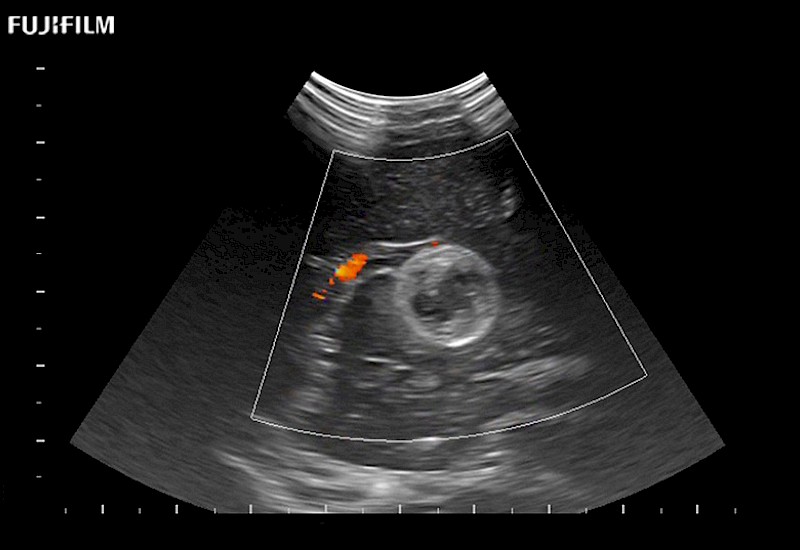

Tight curved (12mm) array transducer that is ideal for scanning during cranial guidance procedures.

Main Specifications: